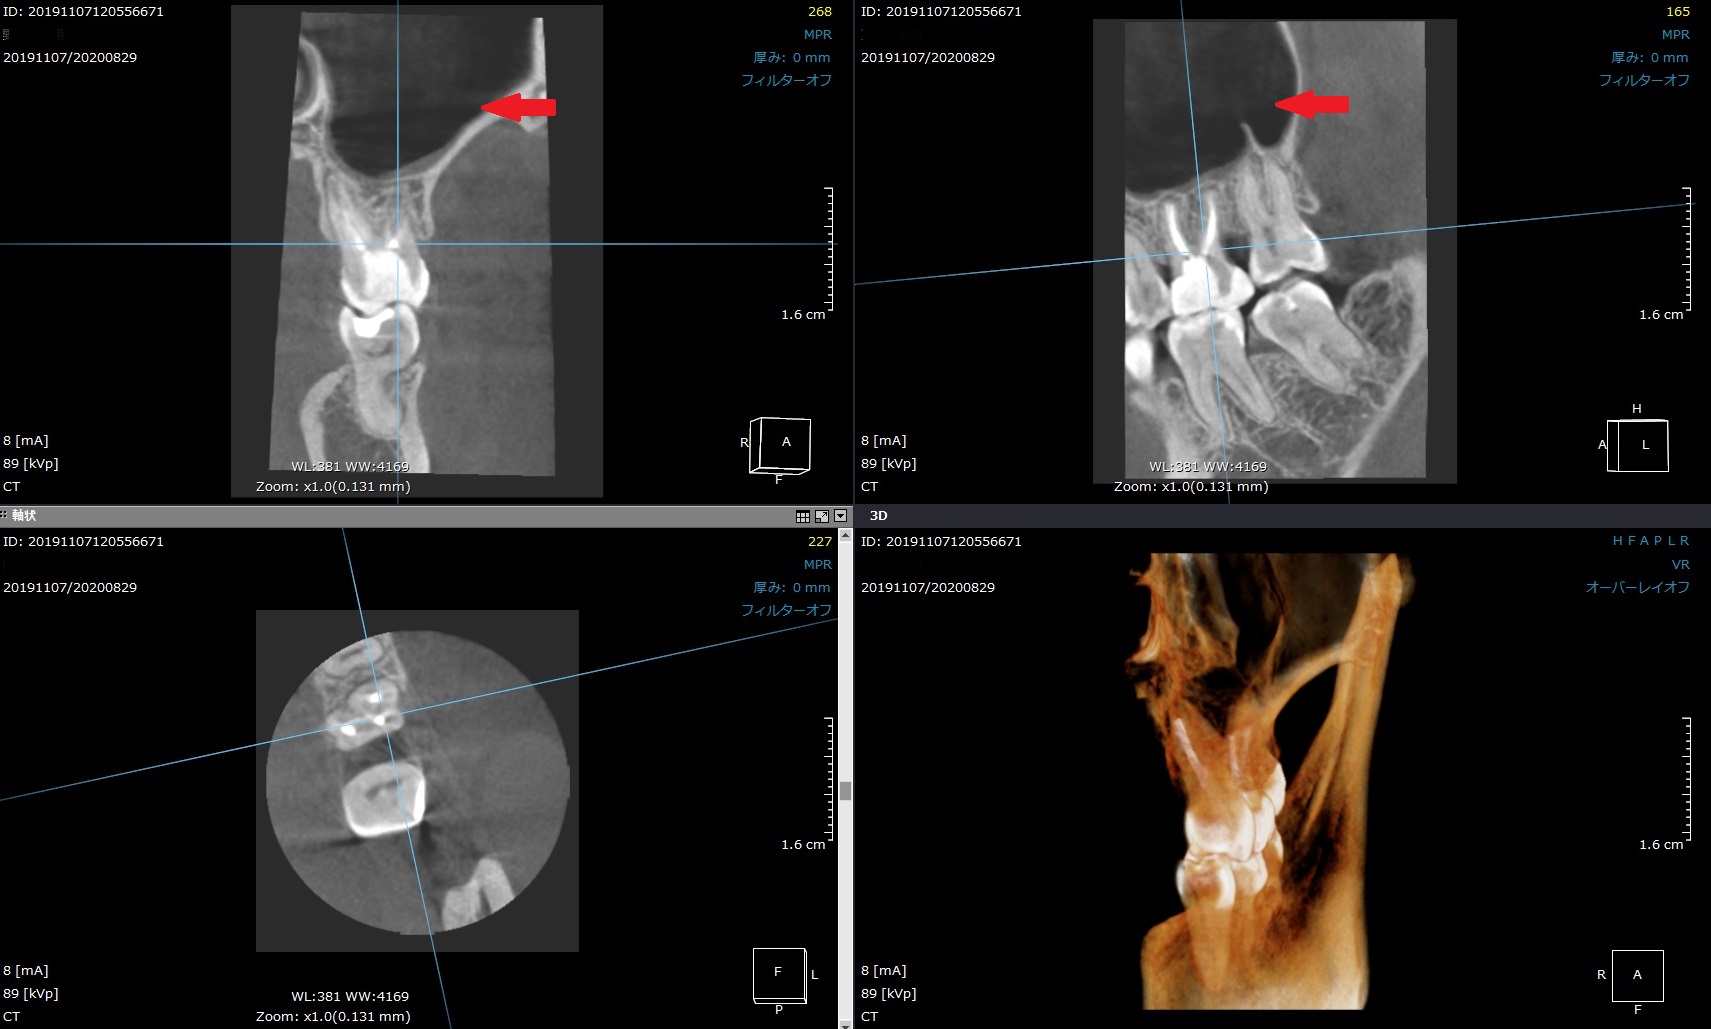

他院で神経を残してもらったが痛みが続く。再治療の治療動画を追加しました②